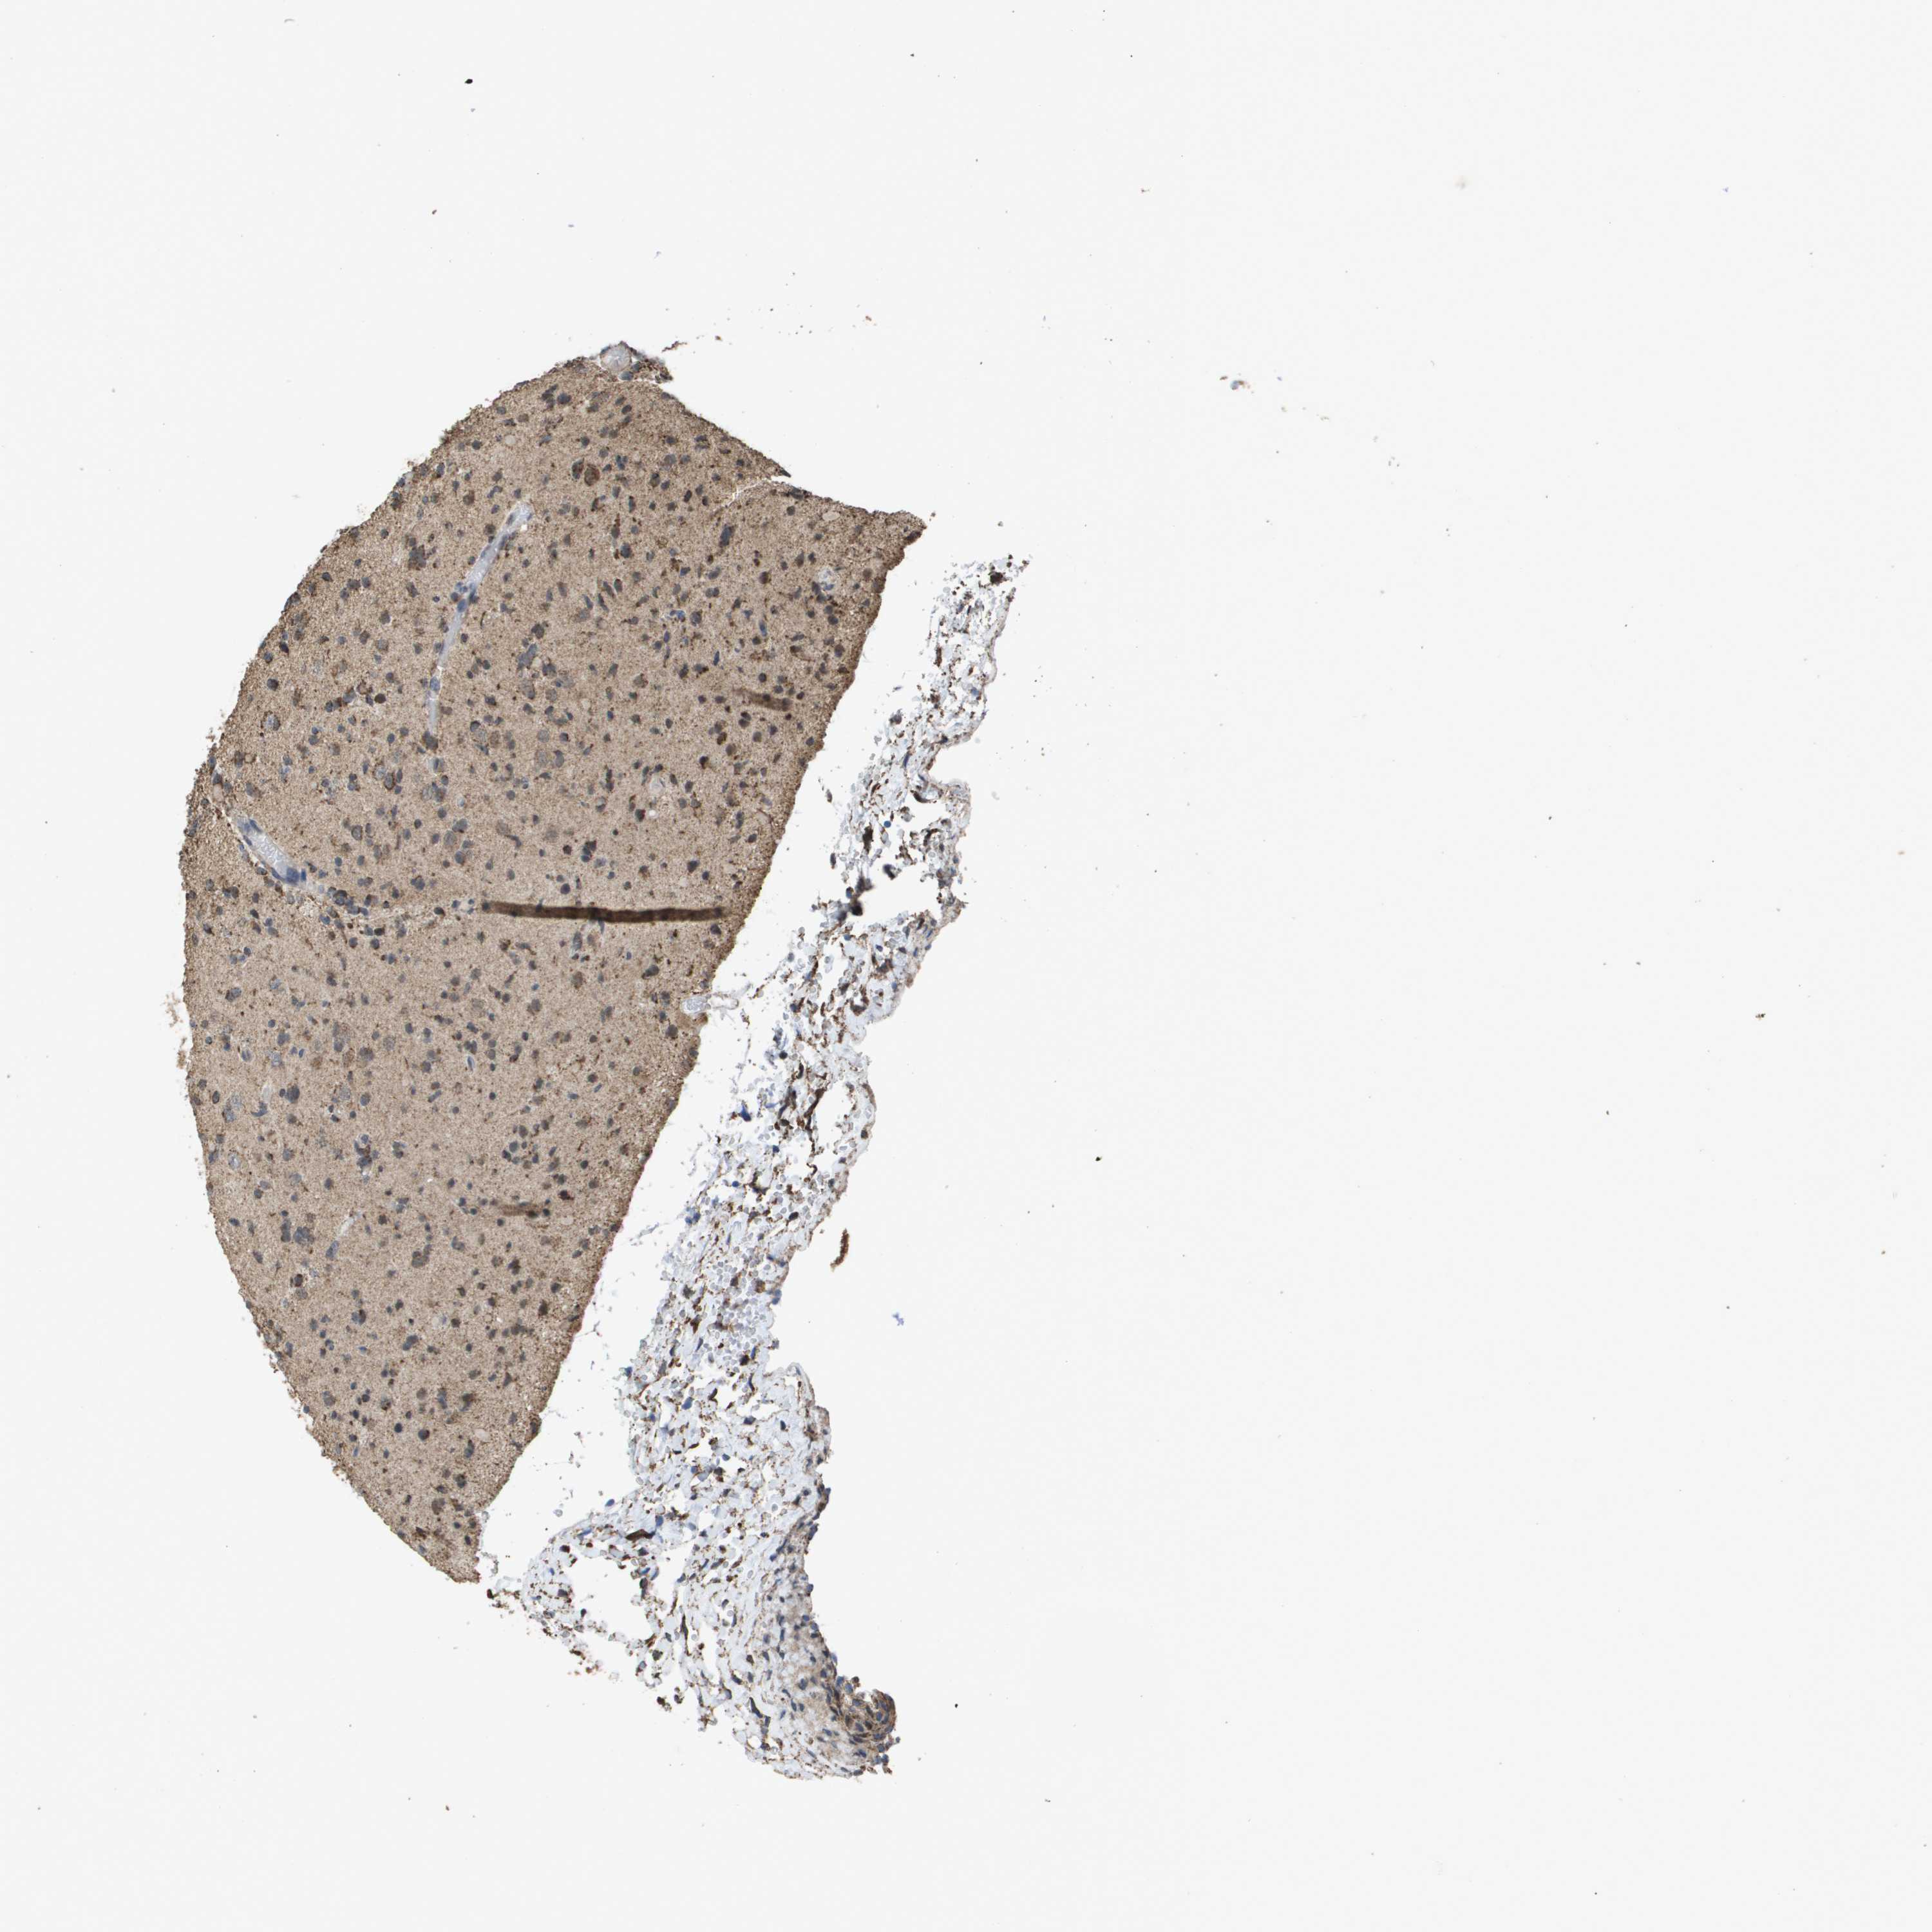

GLIOMA - Protein expressioni

A mouse-over function shows sample information and annotation data. Click on an image to view it in a full screen mode. Samples can be filtered based on level of antibody staining by selecting one or several of the following categories: high, medium, low and not detected. The assay and annotation is described here.

Note that samples used for immunohistochemistry by the Human Protein Atlas do not correspond to samples in the TCGA dataset.

Antibody stainingi

Antibody staining in the annotated cell types in the current human tissue is reported as not detected, low, medium, or high, based on conventional immunohistochemistry profiling in selected tissues. This score is based on the combination of the staining intensity and fraction of stained cells.

Each image is clickable and will lead to virtual microscopy that enables deeper exploration of all samples and also displays staining intensity scores, fraction scores and subcellular localization as well as patient and tissue information for each sample.

Antibody HPA038755

Antibody HPA048272

Antibody CAB017366

Staining

High

Medium

Low

Not detected

Intensity

Strong

Moderate

Weak

Negative

Quantity

>75%

75%-25%

<25%

None

Location

Nuclear

Cytoplasmic/membranous

Cytoplasmic/membranous,nuclear

Glioma, malignant, High grade

Glioma, malignant, Low grade

Glioblastoma, NOS